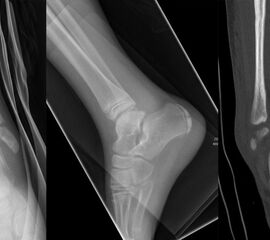

Der teilweise komplexe Frakturverlauf bei Übergangsfrakturen lässt sich im CT zuverlässig darstellen 10. Der erfahrene Untersucher kann bereits mit Röntgenaufnahmen des Sprunggelenks in zwei Ebenen in Verbindung mit zwei 45° Schrägaufnahmen sehr umfassende Aussagen zum Frakturverlauf treffen (v. Laer 2013), die Präzision und Aussagekraft der Computertomografie ist aber zweifelsohne überlegen und wird von den meisten Behandlern bevorzugt 11, auch wenn sich zu diesem Thema in der Literatur eine teilweise sehr emotional geführte Diskussion findet. Einigkeit hinsichtlich der Indikation für ein Schnittbildverfahren besteht bei Triplane-Frakturen, wenn Zweifel darüber bestehen, inwieweit die metaphysäre Fraktur den tragenden Gelenkanteil tangiert 12.

Übergangsfrakturen weisen häufig nur eine geringe Dislokation auf (Abb. 25). Möglicherweise wurden diese Verletzungen in ihrer Rolle hinsichtlich einer Arthroseentwicklung lange Zeit überbewertet 13. Nicht dislozierte Frakturen können konservativ behandelt werden.